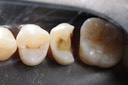

Wes Sato #14 prep